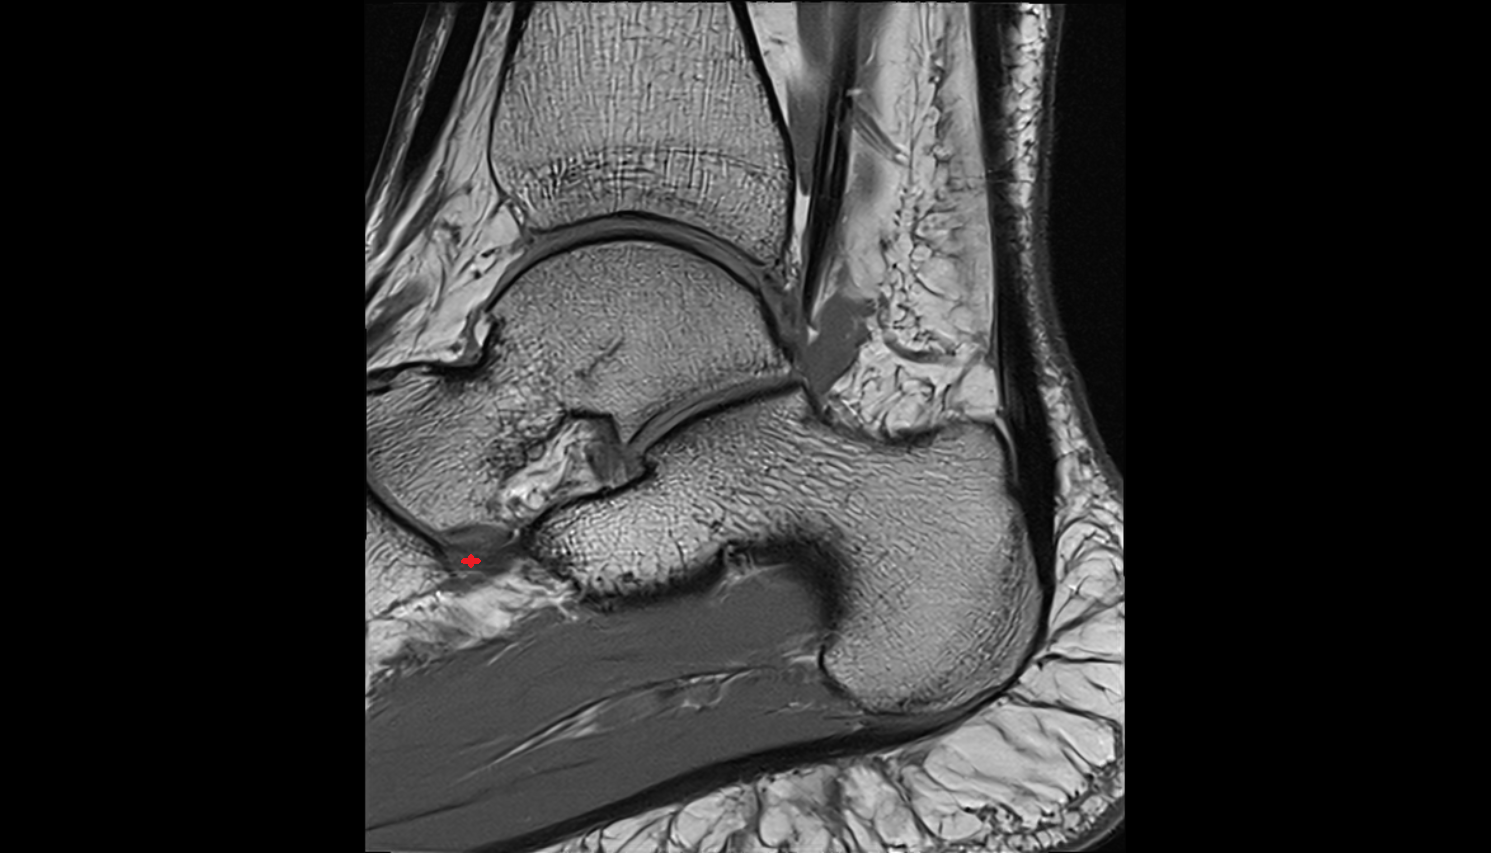

- Talus

- Calcaneus

- Medial malleolus

- Lateral malleolus

- Ankle joint

- Achilles tendon

- Sustentaculum tali